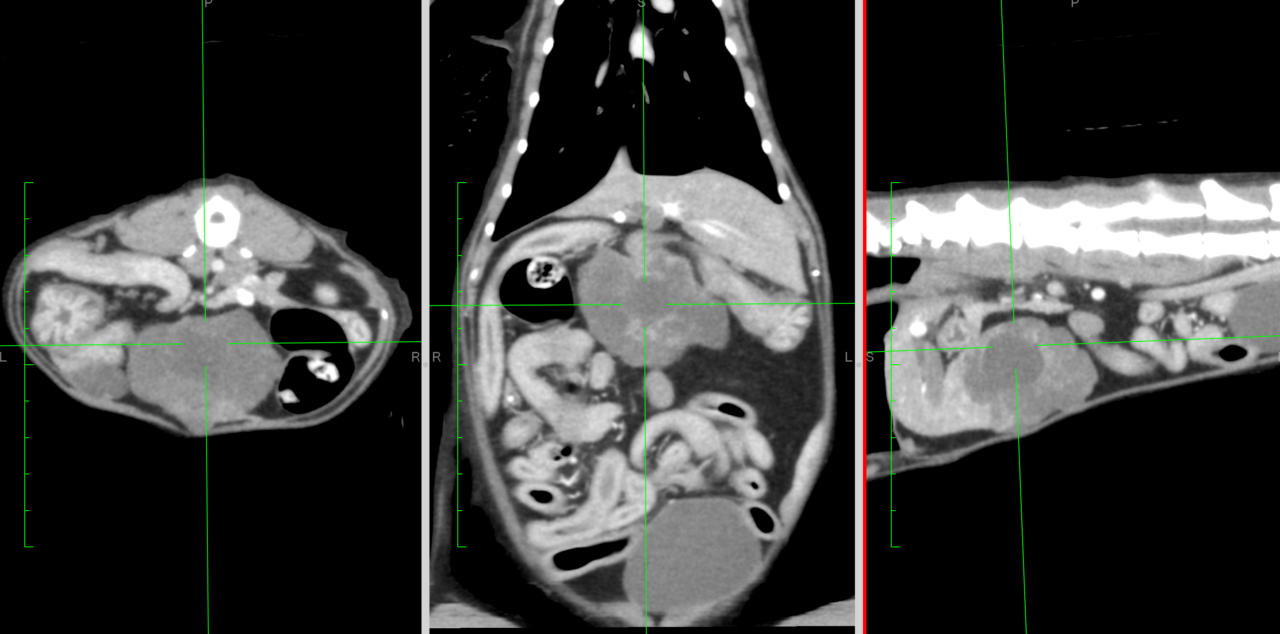

12歳のスコティッシュホールドが食欲不振とのことでかかりつけ医を受診されました。腹部の超音波検査で肝臓にシコリが発見され、CTによる精査と外科的摘出の相談に来られました。CTでは内側左葉が原発の巨大な肝臓腫瘍が疑われました。開腹しTA30Vで一括切除を行いました。腫瘤サイズはこの子の体にとっては巨大であり、解剖学的な位置関係から胃を圧排しており、食欲不振の原因になります。切除後は食欲も徐々に改善傾向にあるとのこと。病理組織的な検索では低悪性度の肝細胞癌とのことであり、今後は再発などをモニタリングしながら経過観察となります。高齢ながら頑張ってくれました。